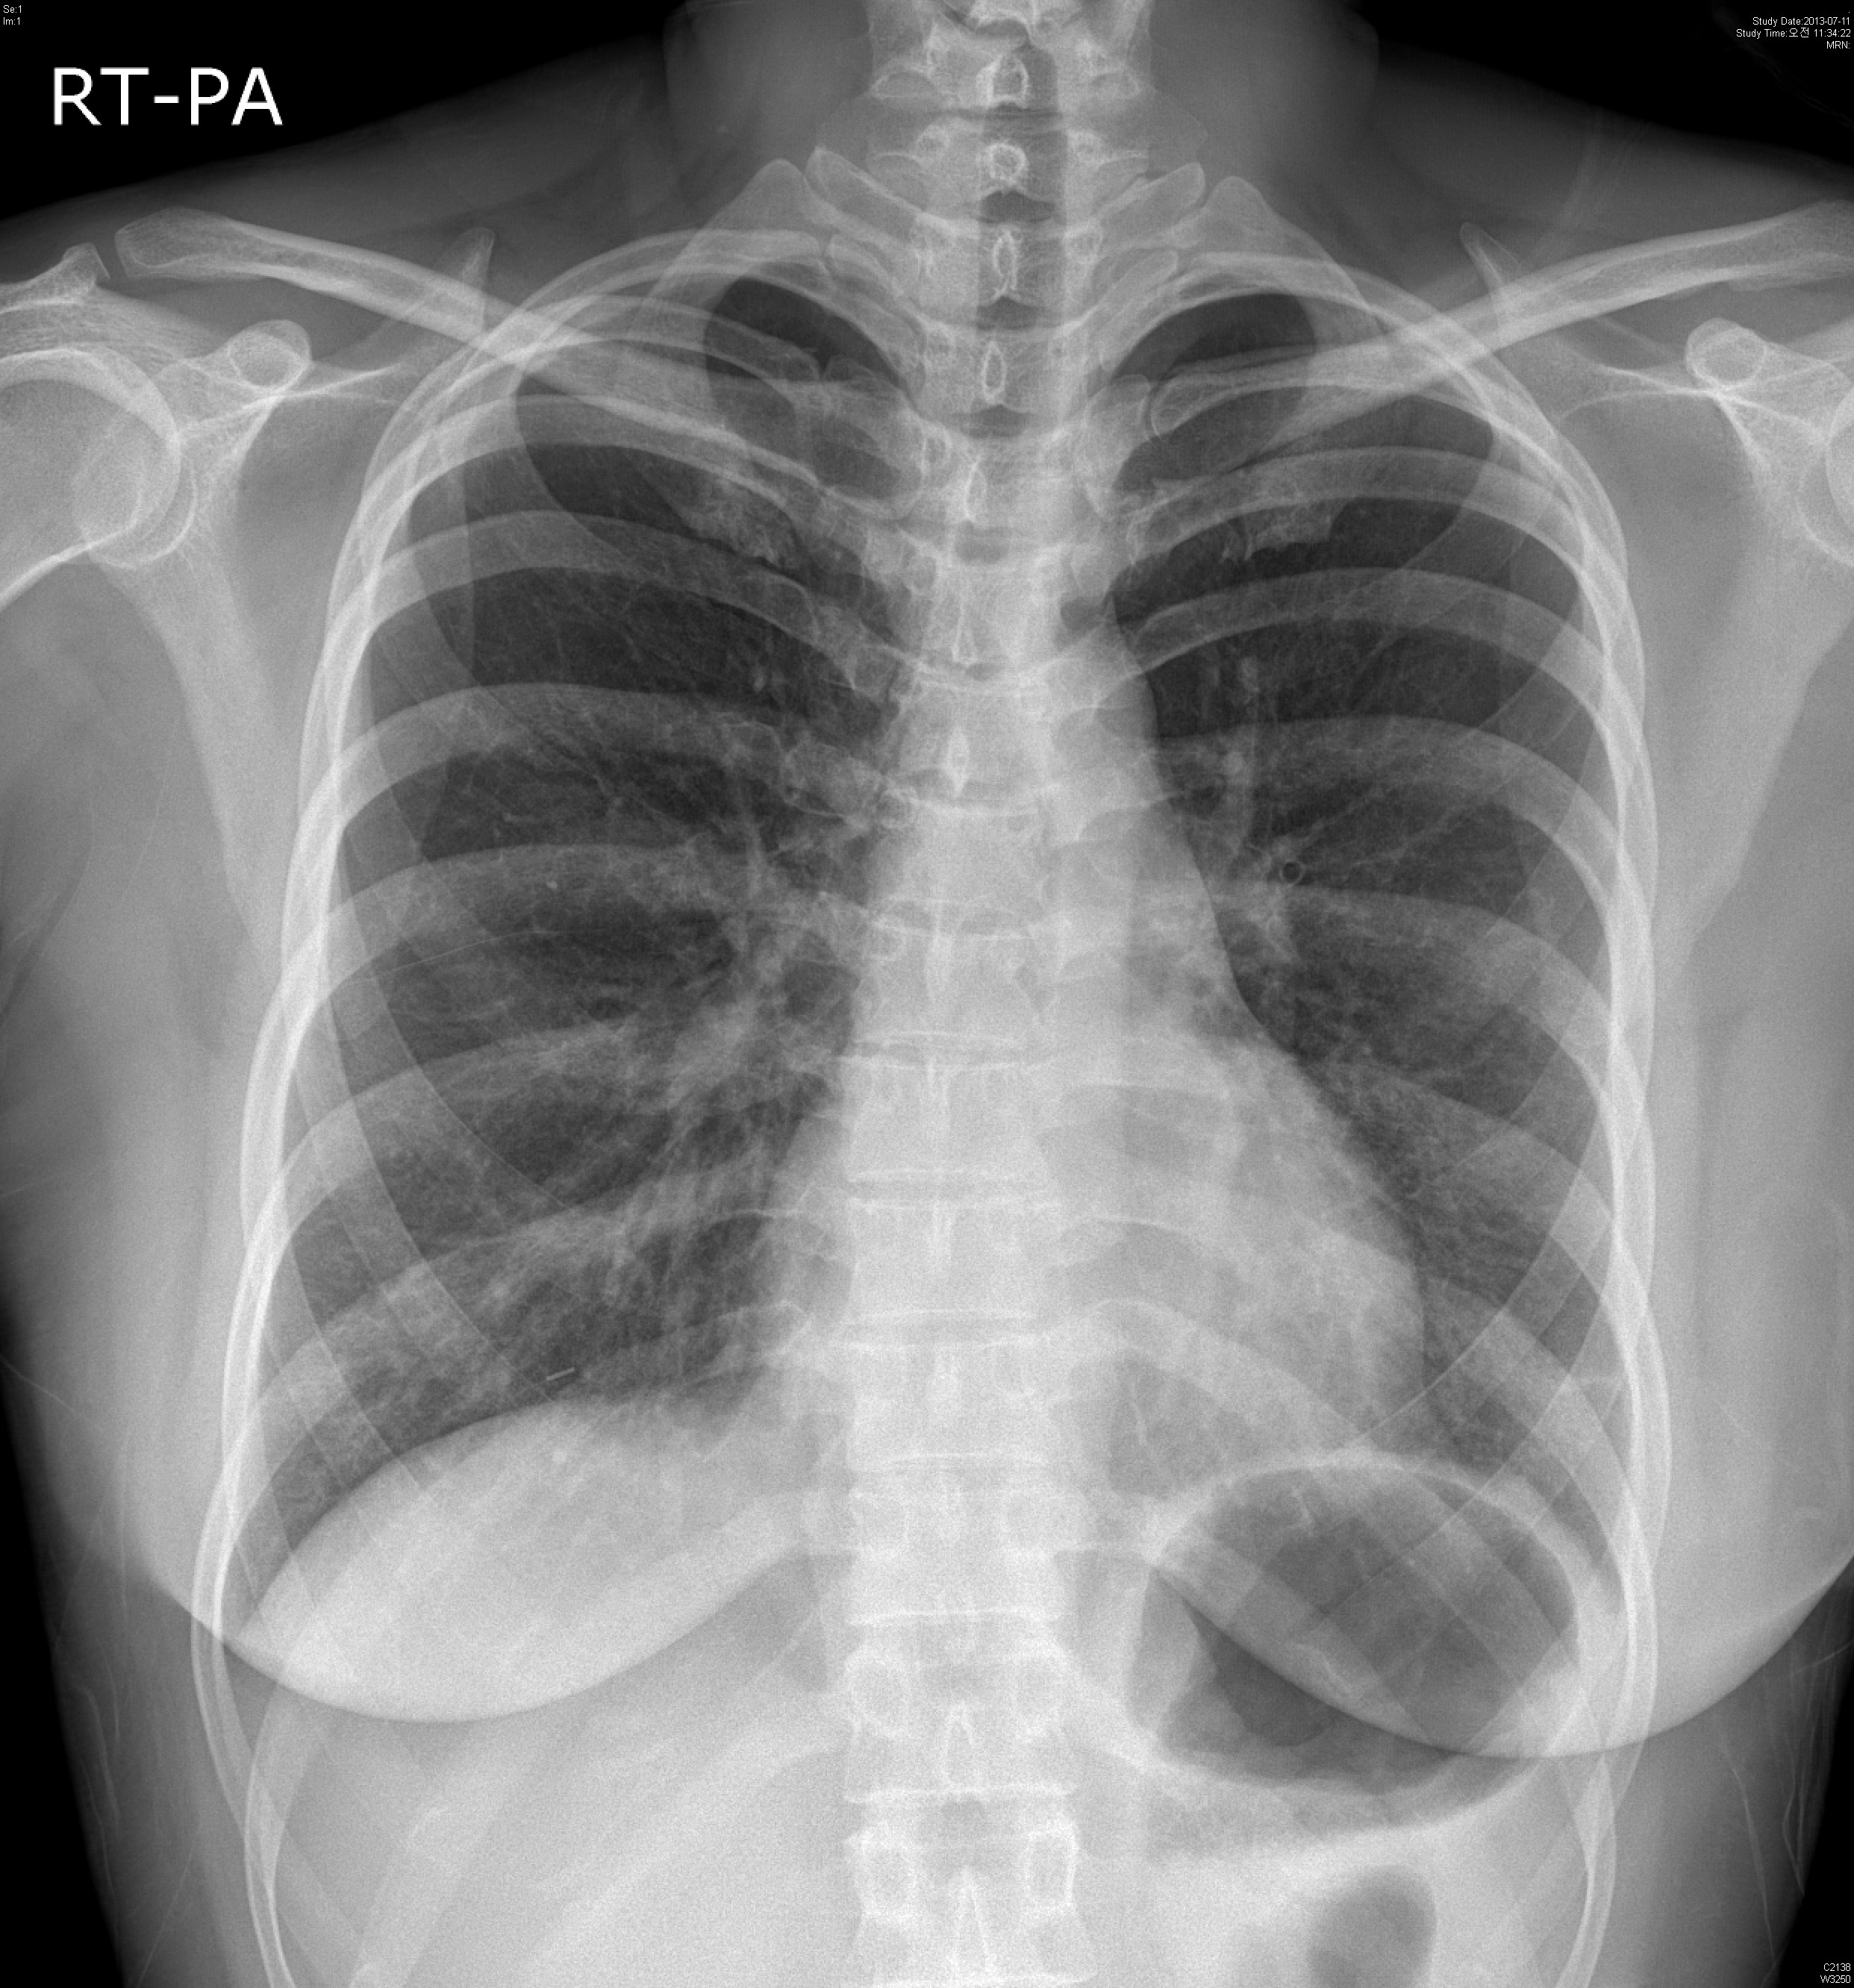

Á¤´ä: Docetaxel induced interstitial pneumonitis

ȯÀÚ´Â breast cancer ¿¡ ´ëÇØ docetaxel based chemotherapy¸¦ ½ÃÇà¹Þ¾Ò°í

ÀÌÈÄ Áõ»ó ¹ß»ýÇÏ¿´½À´Ï´Ù.

Diffuse patchy ground glass opacity in both lungs.

No pleural effusion.

IMP: Most likely interstitial pneumonia such as viral or PCP.

¾Æ·¡´Â Ä¡·á ÀüÈÄÀÇ »çÁø°ú  Review ÀÔ´Ï´Ù.

Docetaxel induced Interstitial pneumonitis